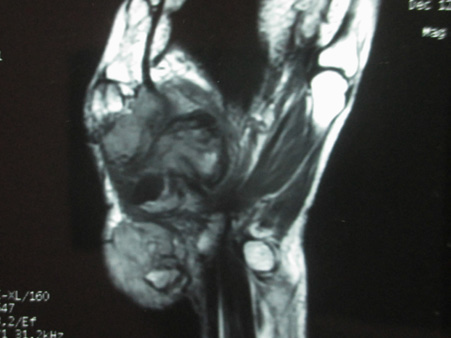

In November 2015 one 60 years lady presented in a newly recognised Medical College of eastern India (Murshidabad Medical College) with recurrence of GCT of the 1st MC of left hand and soft tissue involvement. One year back she was presented in another medical college with intraosseous Capancci grade III lesion of the same site of two years duration where it was treated with narrow margin resection, interposition bone cement on a Kirschner wire (K wire) (Figure 1). It started recurring after 8 months of resection. But presented to us after another one year when extensive extension within soft tissue took place. In plain x ray one small osteolytic lesion was noticed over mid shaft of second metacarpal of the same hand which was not seen in earlier radiographs. MRI was done to identify adjacent bone involvement and to know extent of the lesion in soft tissue (Figure 2). Involvement of regional lymph node and lung metastasis were excluded clinically and radiologically.

Figure 1 a. Initial X-ray initial presentation 3 years back; post-operative X-ray after initial operation; b. immediate; c. subsequent.